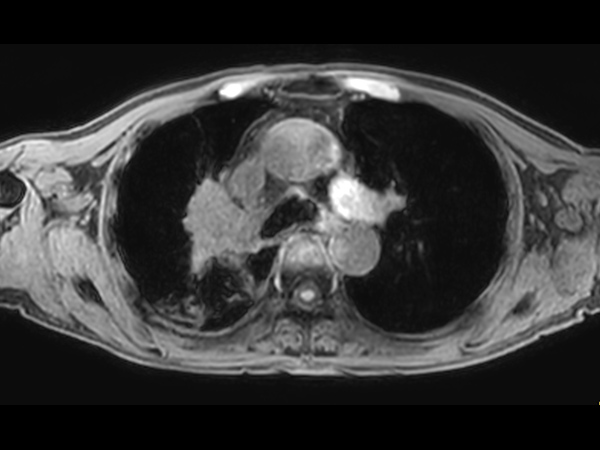

Patient with lung cancer. The ExamCard includes techniques for efficient fat-free imaging over large field-of-views (mDIXON XD), a diffusion procedure with less distortion (DWI TSE XD), a multi-phase contrast-enhanced sequence (4D FreeBreathing) to improve imaging confidence and Compressed SENSE to accelerate the entire exam.

T2w TSE Compressed SENSE

T2w TSE